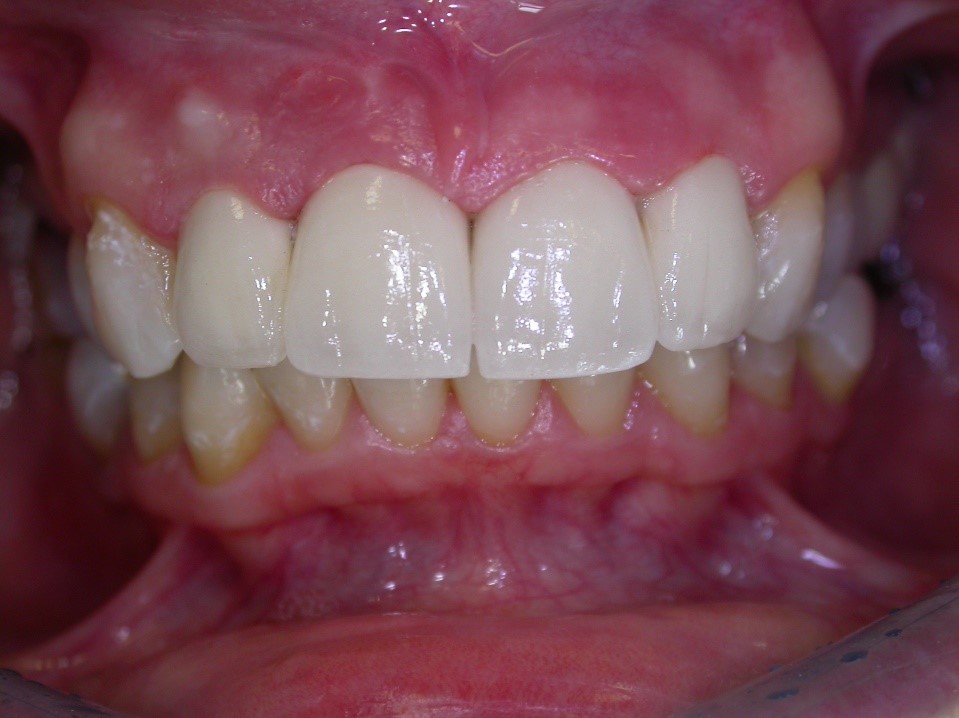

Úprava estetiky chrupu pomocí keramických fazet

Keramické fazety jsou vhodným řešením pro estetickou úpravu přední části chrupu ať již z důvodu tvaru zubů, jejich poškození či trvalého nežádoucího zabarvení. Vyžadují menší preparaci vlastního zubu, jsou také zhotovovány v zubní laboratoři, a proto je potřeba dvou návštěv v ordinaci.

Ukázky naší práce